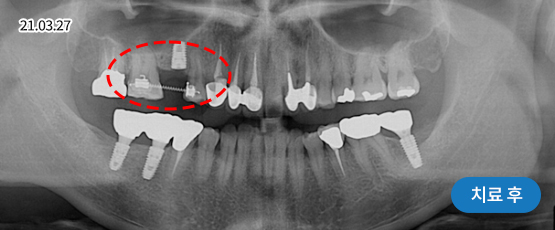

상악동 거상술

잇몸뼈가 없어도 만들어서 식립해 드립니다.

상악동은 윗 잇몸뼈 위쪽의 코 양옆으로 뻥 뚫려 있는 공간이며, 얇은 막으로 덮여 있습니다.

위쪽 어금니 임플란트를 심을 때, 이 부근의 잇몸뼈가 부족하면 임플란트가 상악동을 뚫고 들어갈 수 있습니다.

이를 방지하기 위해 상악동의 얇은 막을 들어 올리고 그 안에 잇몸뼈를 적당히 채워 주는 수술 방법이 상악동 거상술입니다.